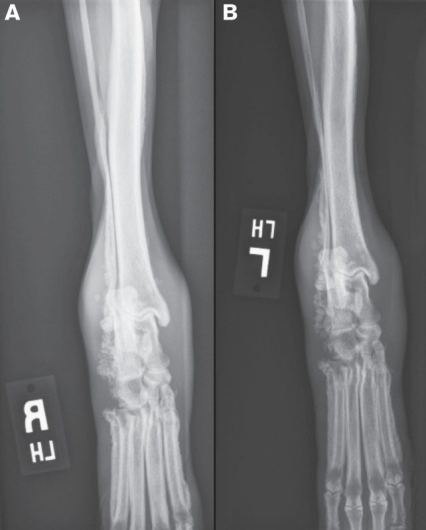

X-ray

- 사지에서 균일한 골막 증상(uniform periosteal proliferation).

- 처음에 Phalanges & metacarpal & metatarsal bones에서 관찰됨.

- 진행됨에 따라 골막 증식은 proximal(ulnar/radius, tibia/fibula)로 진행됨.

- Long bone의 관절 표면은 보통 정상적으로 보임.

- Firm soft tissue swelling of the distal extremities; 말단 사지에 단단한 연조직 부종 형성.

- 양쪽, 대칭적으로 골막 외부에 신생 조직 형성됨 - 초기에는 metatarsal/carpal bones의 축 아래쪽(abaxially)에서 관찰.

- 뼈의 축은 만성적인 경우 영향을 받음.